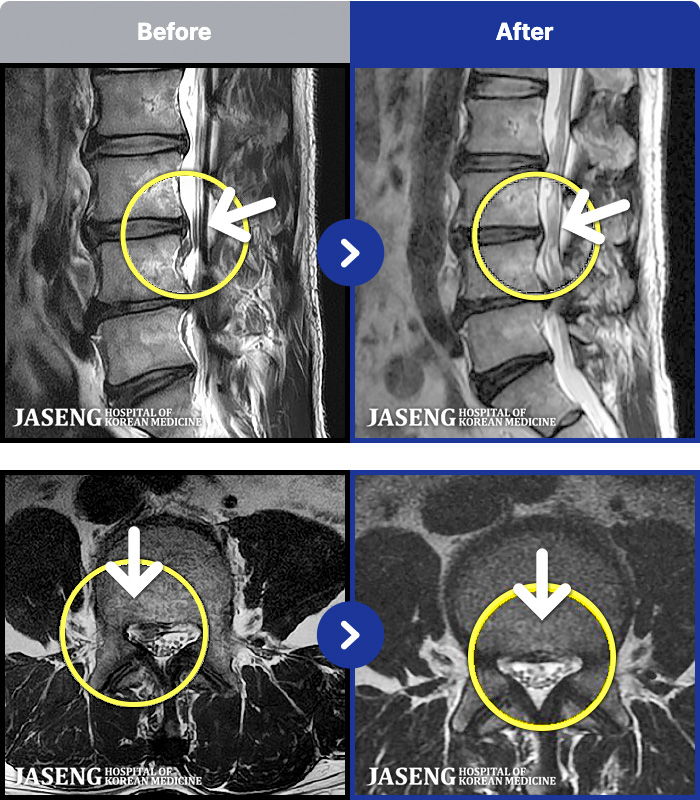

[ϻ] 24.07.25~25.08.01